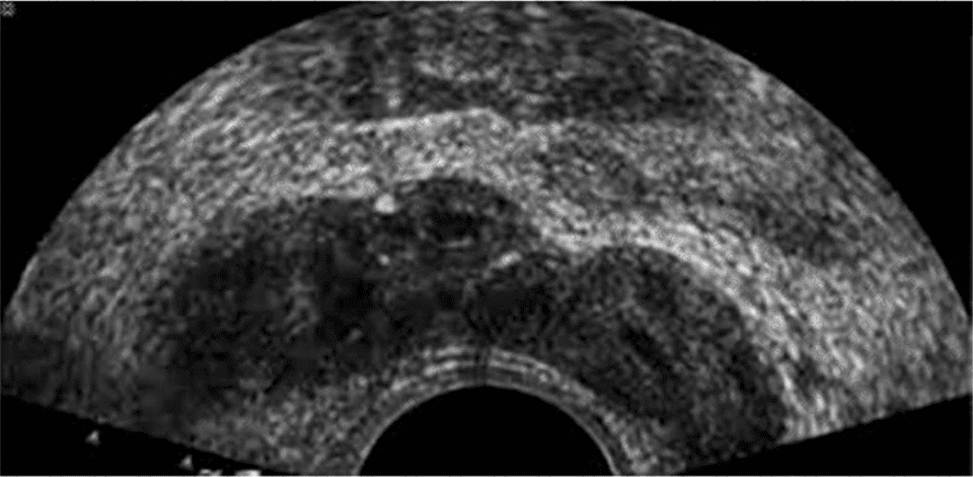

Which anatomical area of the male reproductive system is demonstrated in this endorectal image?

The ultrasound image shown is a transverse endorectal (transrectal) ultrasound, commonly used to evaluate the prostate and adjacent structures. The two hypoechoic (dark) oval-shaped structures seen superior and posterior to the prostate are characteristic of the seminal vesicles.

The seminal vesicles are paired, elongated glands located superior and posterior to the base of the prostate and are best visualized in transverse planes on endorectal imaging. They appear as hypoechoic or anechoic structures with internal septations, depending on the degree of fluid content.

In contrast:

The urethra appears as a central echogenic linear structure within the prostate.

The prostate base is more inferior in the scan and is visualized just above the urethra.

The ejaculatory ducts are usually not as prominently visualized and are located medial to the seminal vesicles, entering the prostate near the verumontanum.

This image most clearly demonstrates the bilateral seminal vesicles.